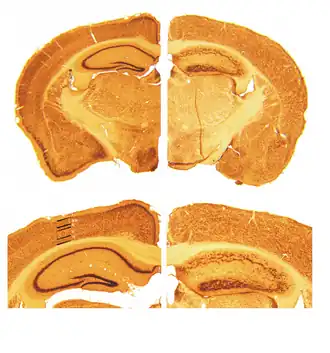

De ontwikkeling van het centrale zenuwstelsel wordt bestudeerd aan de hand van mutaties bij muizen. In 1951 ontdekte Douglas Scott Falconer dat een groep muizen in het lab van Charlotte Auerbach een abnormale wankelende manier van lopen vertoonde. Dit bleek het gevolg te zijn van een verstoorde ontwikkeling van het centrale zenuwstelsel. Deze zogeheten reelermouse vertoonde de afwijking als gevolg van een mutatie van het RELN-gen dat voor reeline codeert. Deze mutatie was homozygoot, wat betekent dat beide kopieën, ofwel allelen van het gen de mutatie droegen. Deze muizen hadden helemaal geen expressie van reeline. Het ontbrekende eiwit reeline werd toen genoemd naar het fenotype en het gedrag van deze muizen die 'wankelden'.[12]

In de jaren '70 werd ook ontdekt dat in een deel van de neocortex van deze muizen de rangschikking van de diverse celtypen en weefsels anders was dan gewoonlijk; in grote lijnen was de volgorde van cellagen omgekeerd, terwijl anderzijds de celdifferentiatie normaal leek te verlopen. De neuroanatomische eigenschappen van de zogeheten reeler-mutant kregen vanaf die tijd meer aandacht.[13]

Muizen met een heterozygote mutatie van het gen voor reeline daarentegen (die een mutatie in slechts één van de twee allelen bezitten) vertonen weinig neuroanatomische afwijkingen ten opzichte van muizen met een homozygote mutatie van dit gen. De hoeveelheid reeline in deze muizen is gehalveerd aangezien het om heterozygote mutaties gaat waarbij slechts een van de twee allelen gemuteerd en dus niet werkzaam is. Om die reden zijn ze interessant als model voor het onderzoek naar psychoses; bij post-mortemonderzoek op psychotische patiënten bleek namelijk dat er in de hersenen sprake was van een downregulatie van 50%.[14]

Embryonale ontwikkeling

Gedurende de embryonale fase speelt reeline een belangrijke rol tijdens de vorming van het centraal zenuwstelsel waar het de neuronale migratie aanstuurt. Eerst wordt in de hersenschors van zoogdieren de "preplaat" opgesplitst in een marginale zone en een tijdelijke subplaat. Tussen deze twee lagen bewegen de neuronen zich volgens het "inside out"-principe waarbij pas gevormde zenuwcellen naar de bovenliggende lagen migreren.[30] Dit is kenmerkend voor de hersenen van zoogdieren; in de zich ontwikkelende hersenschors van reptielen migreren de zenuwcellen in de omgekeerde richting. Een reelinetekort bij zoogdieren heeft dan ook tot gevolg dat de uiteindelijke volgorde van de hersenschorslagen min of meer wordt omgedraaid en hetzelfde is als in reptielen, zoals het geval is met de reelermouse, de muis waarin voor het eerst de gevolgen van het reelinetekort bekend zijn geworden.[31]

- Corticogenesis bij muizen. Geraadpleegd op 23 augustus 2008. “Pictorial rendition of the difference that the lack of reelin brings to the cortical structure” – A figure from Magdaleno SM, Curran T (december 2001). Brain development: integrins and the Reelin pathway. Curr. Biol. 11 (24): R1032–5. PMID 11747842. DOI: 10.1016/S0960-9822(01)00618-2.